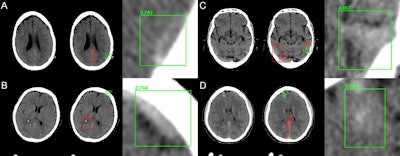

Mask residual CNN architectures can provide a framework for parallel evaluation of region proposal (attention), object detection (classification), and instance segmentation. In this approach, (A) preconfigured bounding boxes at various shapes and resolutions are tested for the presence of a potential abnormality. (B) The highest ranking bounding boxes are identified and used to generate region proposals that focus algorithm attention. (C) Composite region proposals are pruned using nonmaximum suppression and used as input into a classifier to determine presence or absence of hemorrhage. (D) Segmentation masks are generated for positive cases of hemorrhage. All images courtesy of Dr. Peter Chang.After fivefold cross-validation, the CNN yielded a high level of performance for detecting hemorrhage on the 10,159 exams. The algorithm missed only 26 (2.9%) of the 901 hemorrhages in the study, with similar performance across all sizes and types.

Network predictions by the algorithm include bounding box region proposals for potential areas of abnormality (to focus algorithm attention) and final network predictions -- including confidence of the result. Correctly identified areas of hemorrhage (green) include subtle abnormalities representing subarachnoid (A), subdural (B and C), and intraparenchymal (D) hemorrhage. Correctly identified areas of excluded hemorrhage often include common mimics for blood on noncontrast CT including thickening/high density along the falx (A, B, and D) and beam hardening along the peripheral brain convexity (D).The mask residual CNN component of the deep-learning architecture can generate volume calculations of the hemorrhages that correlate highly with ground-truth measurements, according to Chang.